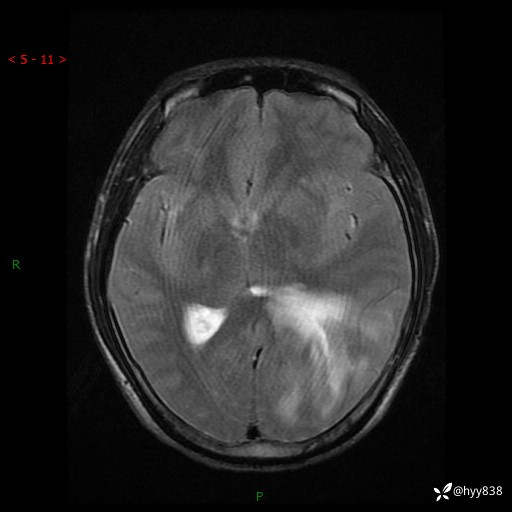

病例年轻小伙,头痛伴呕吐半年,渐进性加重1月。疑难病例,第一次见--结果公布~

性别:男

年龄:21岁

简要病史:头痛伴呕吐半年,渐进性加重1月

颅脑MRI平扫+增强